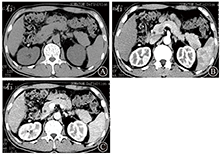

患者男,52岁,因乏力、纳差、尿黄7 d入院。患病以来胃纳明显减退,无腹痛、腹泻、恶心、呕吐、胸闷、气急等。门诊检查肝功能:TBil为33.7 μmol/L,DBil为17.9 μmol/L,ALT为73 U/L,AST为249 U/L。10年前曾行胆囊切除术,有戊型肝炎史。于2014年11月27日以慢性肝病收入院。体格检查:体温36.8 ℃,脉搏77次/min,呼吸19次/min,血压115/75 mmHg(1 mmHg=0.133 kPa)。皮肤、巩膜轻度黄染,浅表淋巴结无肿大,全身未见蜘蛛痣,未见肝掌。两肺呼吸音清,未闻及干、湿性啰音。心律齐,未闻及病理性杂音。全腹平软,腹壁无曲张静脉,全腹无压痛及反跳痛,肝区叩击痛阳性,肝脾肋下未及,墨菲征阴性,移动性浊音阴性,肠鸣音无亢进,双下肢无水肿。上腹部CT示,胰腺尾部一直径为1.2 cm类圆形病灶,平扫与胰腺等密度,动脉期病灶强化较胰腺低,呈不均匀强化,门静脉期强化均匀,与胰腺等密度(图1)。MRI示,胰尾部一直径1.2 cm类圆形病灶,T1加权像呈均匀低信号,T2加权像、弥散加权成像呈高信号,表观弥散系数呈低信号,在所有扫描序列与主脾信号相似,动脉期呈不均匀强化,门静脉期呈均匀强化(图2)。AFP、CEA正常,CA19-9 49.4 U/mL(参考范围为0~39 U/mL),烯醇化酶21.1 μg/L(参考范围为0~12.5 μg/L)。入院后给予复方甘草酸苷、丁二磺酸腺苷甲硫氨酸、熊去氧胆酸护肝退黄利胆治疗,于2014年12月22日在全身麻醉下行腹腔镜胰尾肿瘤+脾切除术,术后病理报告胰尾异位脾。

胰腺内异位副脾影像学通常表现为胰尾部光滑圆形、类圆形或浅分叶肿块,边界清楚。CT平扫表现为等密度或稍低密度,增强动脉期不均匀强化,门静脉期、延迟期强化均匀,与脾强化相似。MRI所有序列信号特点与主脾相似,与正常胰腺实质相比,T1加权像呈低信号,T2加权像呈高信号,弥散加权成像呈高信号,增强强化特点与CT相似,表现为动脉期不均匀强化,门静脉期、延迟期均匀强化。使用超顺磁氧化颗粒特异性MRI对比剂可提高胰腺内异位副脾的诊断准确性。胰腺内异位副脾典型影像学诊断并不困难,但主脾切除后或异位副脾内合并表皮样囊肿时会给诊断带来难度。因囊肿内壁光滑,所以寻找囊肿周围副脾组织是诊断关键[2] 。胰腺内异位副脾还需与胰尾部富血供肿瘤鉴别。胰腺囊实性乳头状瘤好发于20~40岁女性,有完整包膜,肿瘤内囊变、出血常见;CT、MRI示肿瘤内部密度、信号不均,MRI可显示肿瘤边缘低信号。胰腺神经内分泌肿瘤因具有特征性临床表现,易被早期发现,肿瘤体积较小,增强动脉期均匀强化或环形强化,门静脉期强化等于或低于胰腺。黑色素瘤、平滑肌肉瘤、肾癌等胰尾转移性肿瘤常表现为富血供,平扫肿瘤呈低密度,增强表现为动脉期不均匀强化,门静脉期强化常低于胰腺。与富血供肿瘤鉴别困难时,超顺磁氧化颗粒信号减低可有助胰腺内异位副脾的诊断。